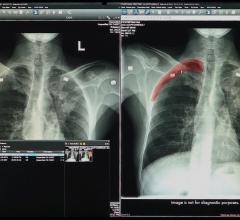

This channel includes information technology (IT) news and new technology innovations for healthcare information technology (HIT) as it relates to electronic medical records, clinical decision support, advanced imaging visualization, analytics software, cybersecurity, archive and storage, artificial intelligence, enterprise imaging, flat panel displays, imaging software, picture archive and communication systems (PACS), remote viewing, teleradiology and vendor neutral archives (VNA).